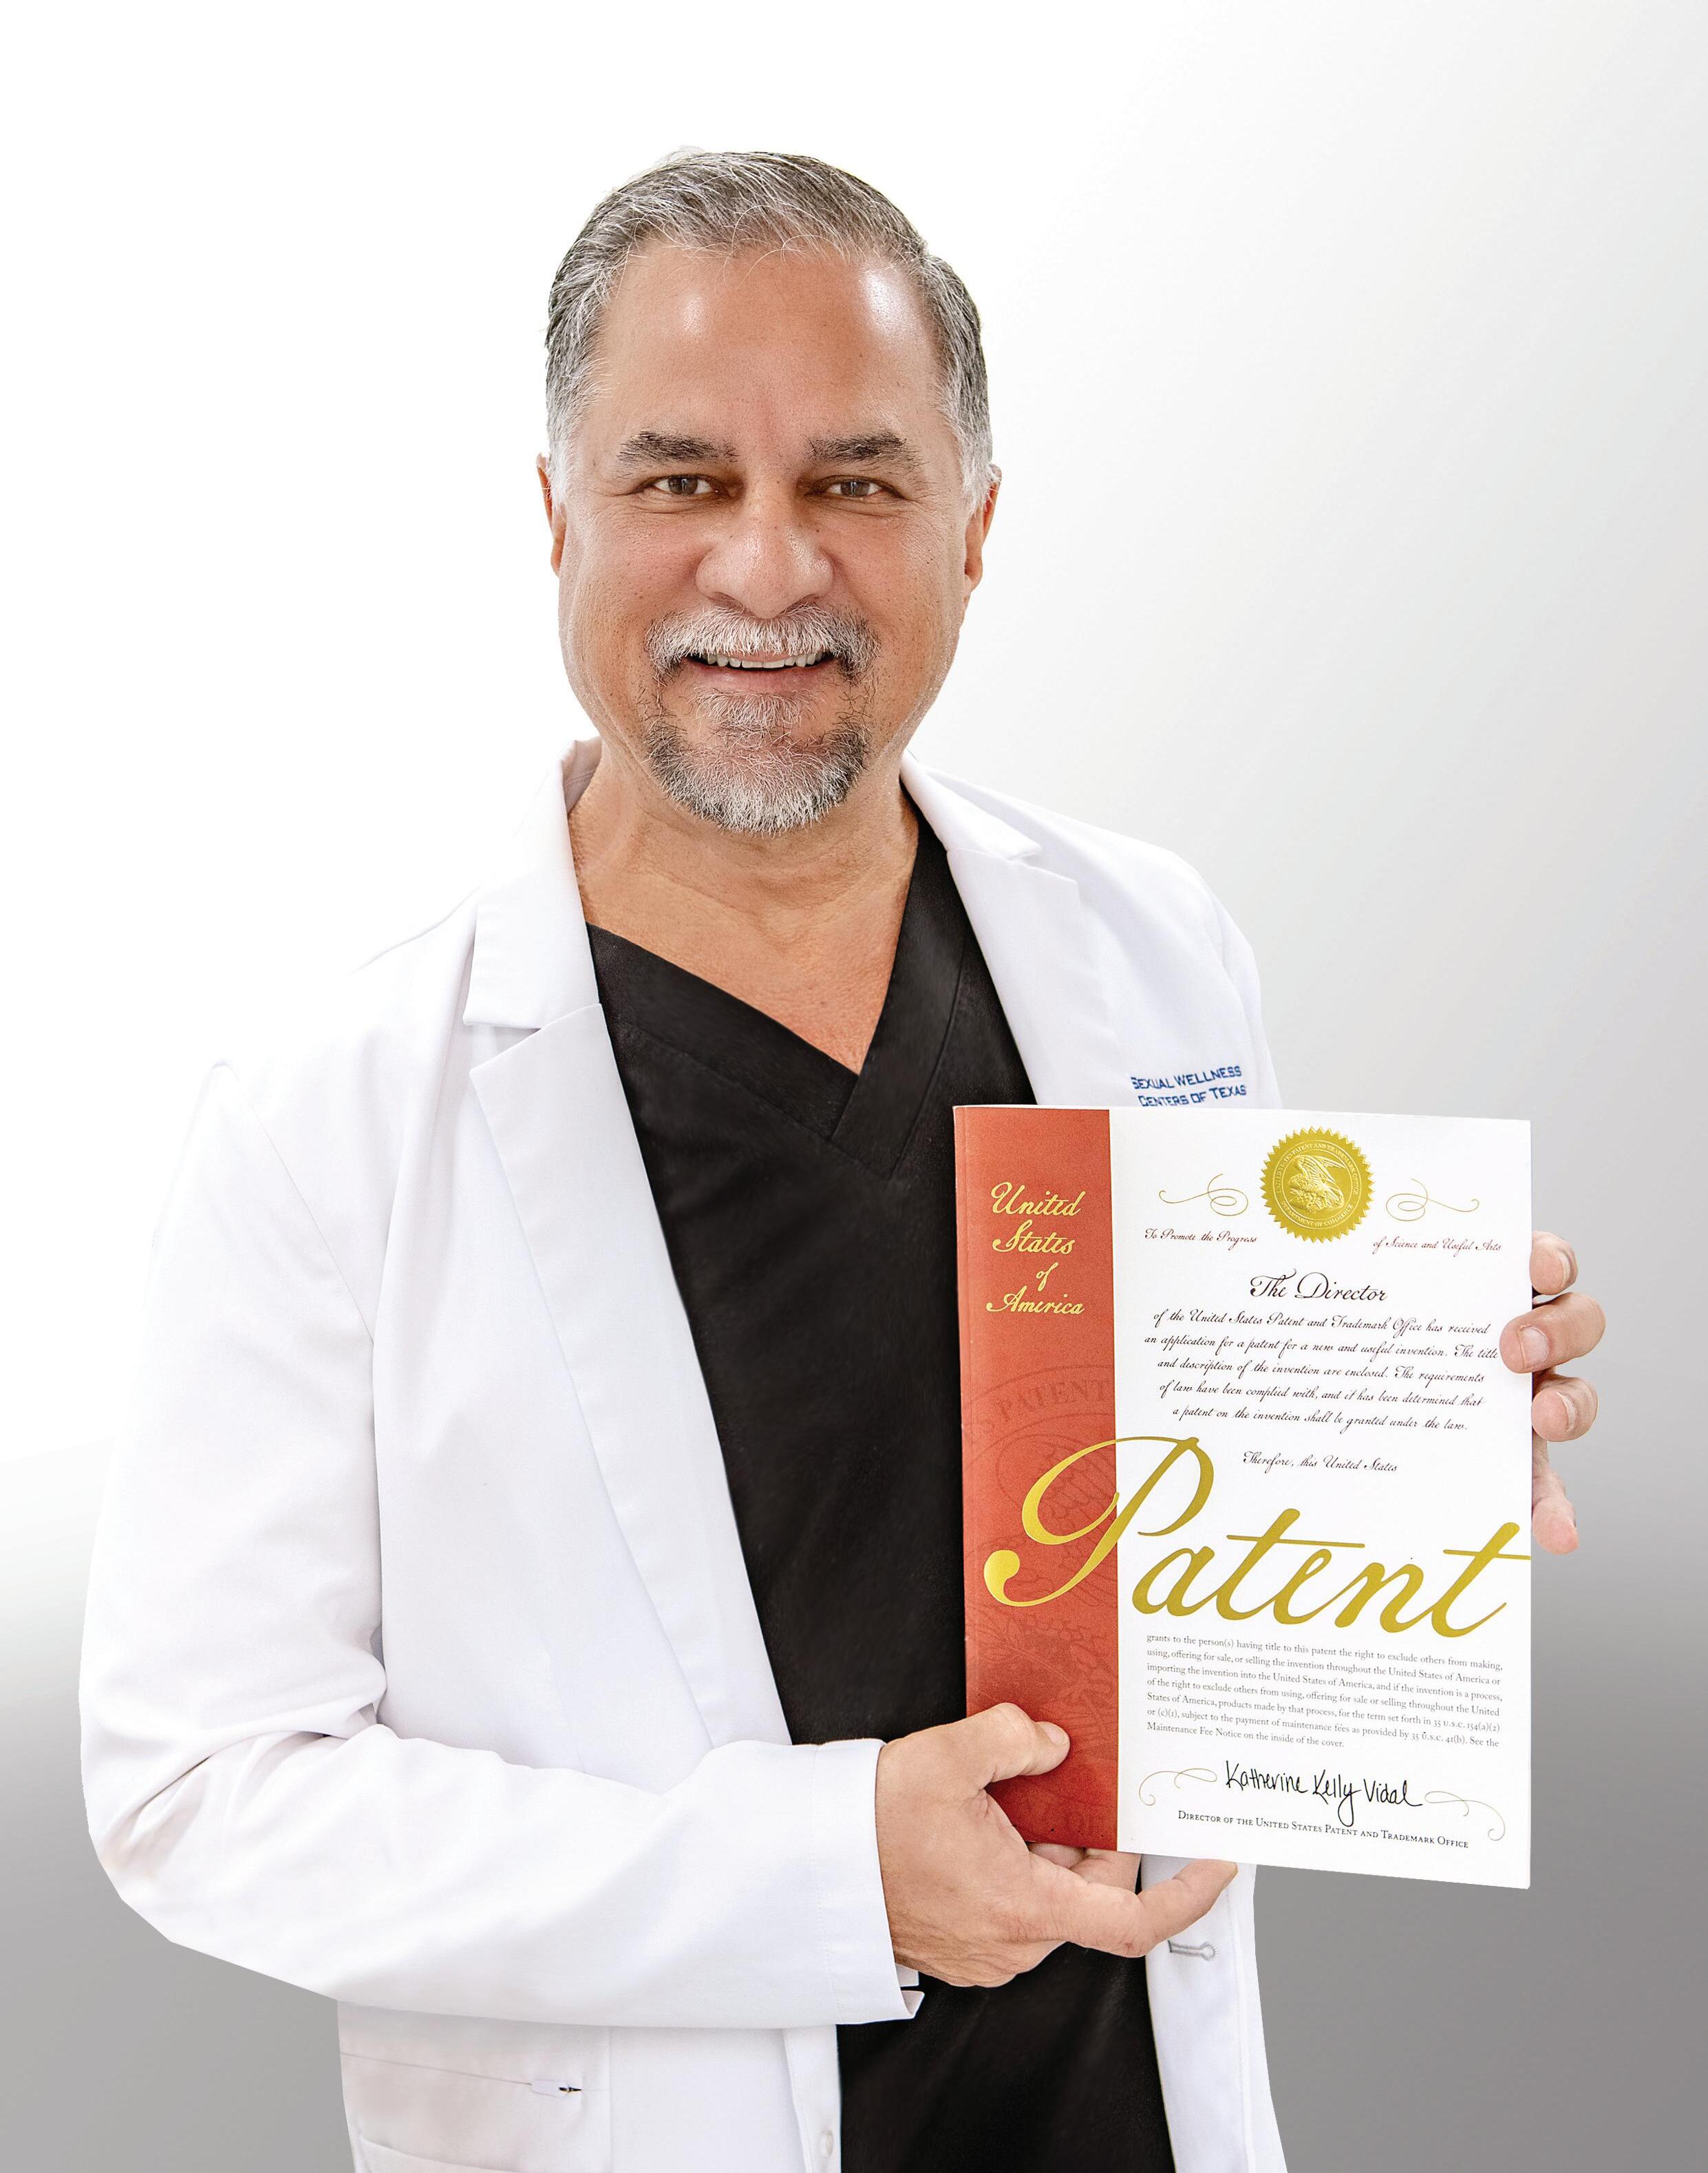

SEXUAL WELLNESS CENTERS OF TEXAS

Specialty | As a medical practice dedicated to sexual health, Sexual Wellness Centers of Texas (SWC) proudly serves patients with patient-focused care and cutting-edge techniques and technologies. SWC was founded with one mission—to rejuvenate your body, boost your energy, increase self-confidence, and help you enjoy your sexuality even in advanced years. Their team is committed to having a holistic approach to caring for, managing, and treating your sexual health. With a commitment to innovation and effective treatment options, SWC is proud to introduce the REGENmax protocol—offering a non-invasive and highly successful cure for ED (erectile dysfunction).

Why Choose SWC | Over the last 15 years and a significant investment in both scientific and clinical studies, a team of SWC MDs and PhDs diligently researched and optimized the REGENmax protocol. Having successfully treated countless patients at their Frisco and Colleyville, Texas locations for years, SWC conducted a formal clinical study of over 250 patients and employed the REGENmax protocol. Results showed 243 patients had reversed their ED after a one-year follow-up, an astounding 97.2% success rate.

REGENmax Protocol | SWC proudly announces the first and only worldwide US patent for the cure of Erectile Dysfunction (ED) and global registered trademark of the REGENmax® protocol. This revolutionary protocol completely reverses ED. You heard that right—it’s a cure. It is important to understand that this is not a pill. It’s not a temporary fix. It’s a painless patent protected procedure with a 97% success rate and quick results.

Life Changing | About 30 million men in the U.S. alone today are suffering from this common issue... they share feelings of hopelessness, shame, worthlessness to themselves and for their partners. ED treatment benefits include a renewed sense of confidence and intimacy for individuals facing challenges with sexual health. Seeking ED treatment not only addresses physical aspects, but also contributes to overall emotional and relational well-being, thus promoting a more fulfilling and satisfying lifestyle.

Patent Protected Procedure | Groundbreaking protocol in a 250-patient study demonstrated effectiveness in eradicating ED—providing a treatment protocol and medical solution for the over 56 million worldwide suffering unnecessarily from this debilitating condition. ED significantly impacts quality of life and self-esteem. Until now, available treatments often relied on pills or surgery, resulting in inconsistent, costly, and temporary results. The REGENmax protocol has solved the root causes of ED through a multi-faceted approach—with absolutely no need for pills or surgical intervention.

Successful Solution | This innovative approach promises to significantly deliver treatment success for ED patients of practice owners, medical providers and clinicians. By integrating REGENmax into their existing protocols, medical practices can offer patients a more cost-effective and non-invasive solution for addressing the root causes of erectile dysfunction.

What You Can Expect | A physical exam and a blood analysis will be performed during your consultation to help the team determine what may be the underlying cause of your sexual dysfunction. Your specific treatment plan will be tailored to meet your unique needs. Some of the available treatments that may be included in your treatment plan include REGENmax for both men and women, HEshot or SHEshot to enhance sexual performance, hormone replacement therapy, ED laser, REGENwave, and more. The goal at SWC is to optimize your personal hormonal levels and this is different for every body.